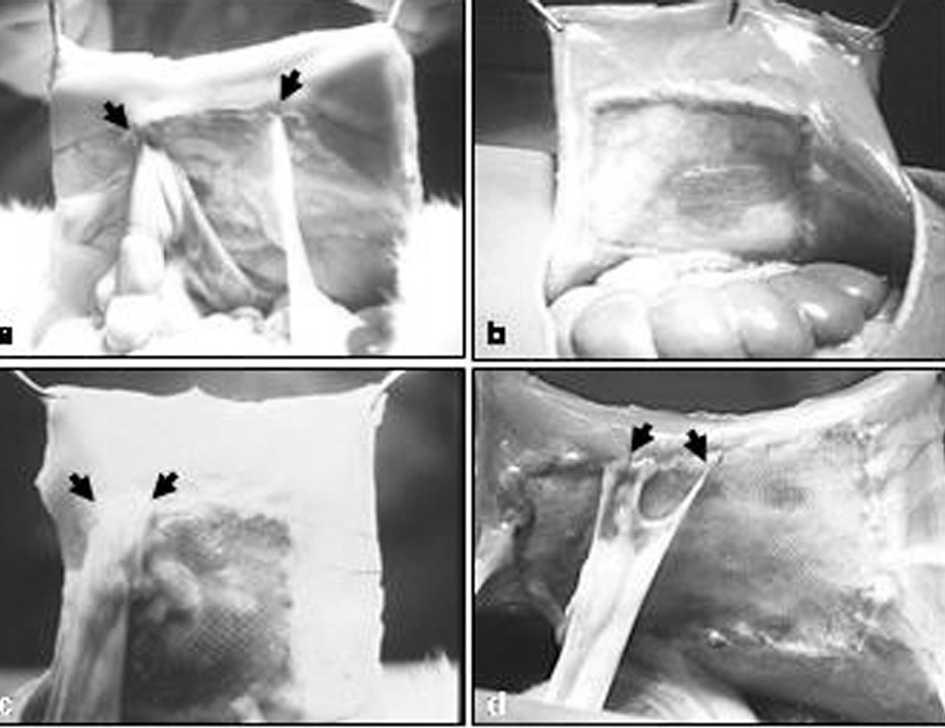

La consistencia de las adherencias fue en todos los implantes de características laxas y en algunos casos estaban ubicadas en la zona de la interfaz prótesis/tejido receptor (fig. 1).

Fig. 1. Fotografía macroscópica de las adherencias: a) PL + PTFEe; b) PL + PU; c) PO + gl; d) PL + hial. PL: polipropileno; PTFEe: politetrafluoroetileno expandido; PU: poliuretano; PO: polietilenglicol; gl: glicerol; hial: ácido hialurónico.

El área ocupada por las adherencias fue: en el grupo A (PL + PTFEe, 010 ± 0,13 cm2; PL + PU, 0,10 ± 0,07 cm2) y en el grupo B (PO + gl, 0,11 ± 0,02 cm2; PL + hial 6,53 ± 1,41 cm2). No hubo diferencias significativas entre las prótesis con barrera física (p > 0,05), pero sí entre las de barrera química (p < 0,05), y el área adherencial fue significativamente mayor en la prótesis PL + hial.